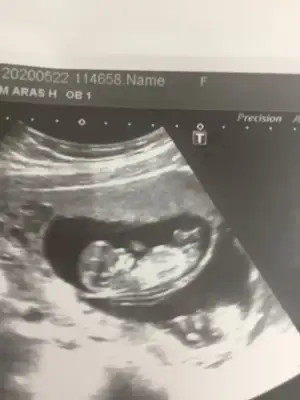

Usg net değil başka varsa paylaşınKizlarr banada yardımcı olun lutfenn sabahtandir kaçıncı yazisim bilenler bana da baksın lütfen çok merak ediyorumEki Görüntüle 2639800

Nubu çok karışık canım ama sanki kafa yapısı erkek gibiYok maaleeef tekrar çekip atayım bir bakın meraktan olcem 12 haftaligiz doktor kemik yapısını kıza benzetti ama birde sizden öğrenmek istedim bebek bir türlü dönmedi ancak bunu cekebildi doktor Eki Görüntüle 2639808 Eki Görüntüle 2639808